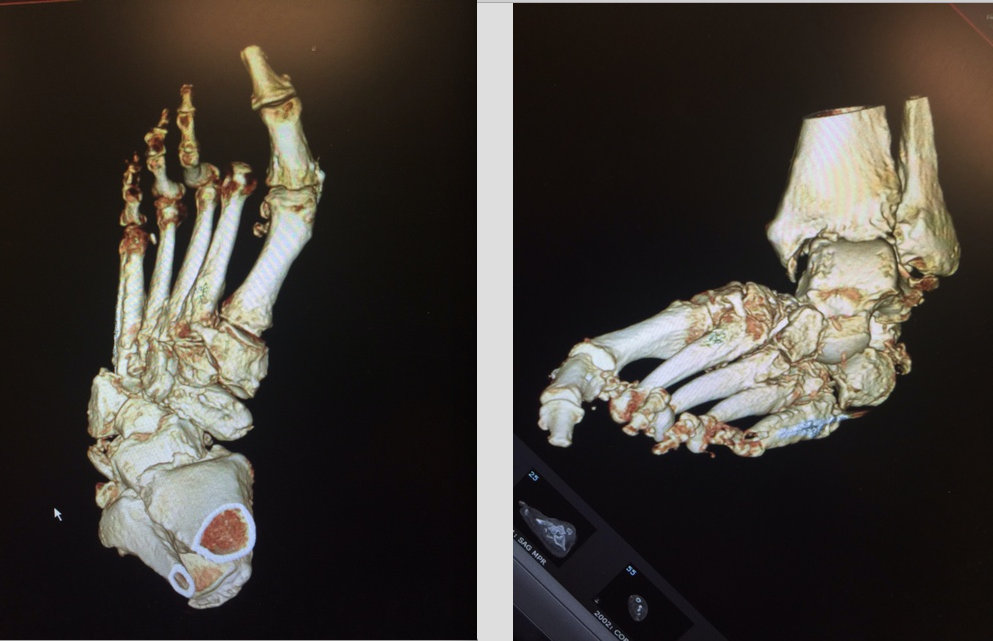

Additionally, the titanium truss is filled with autogenous bone graft and orthobiologics, allowing for incorporation through the osteotomy site. This device allows for reconstruction in situations of excessive bone loss, acting as a replacement with the capacity for ingrowth. Follow-up demonstrates improved angular deformity correction with complete bridging on computed tomography (CT) scan.

Within these aforementioned confines, we believe the use of beam screws with titanium truss wedges can be an additional superconstruct that surgeons can add to their arsenal.